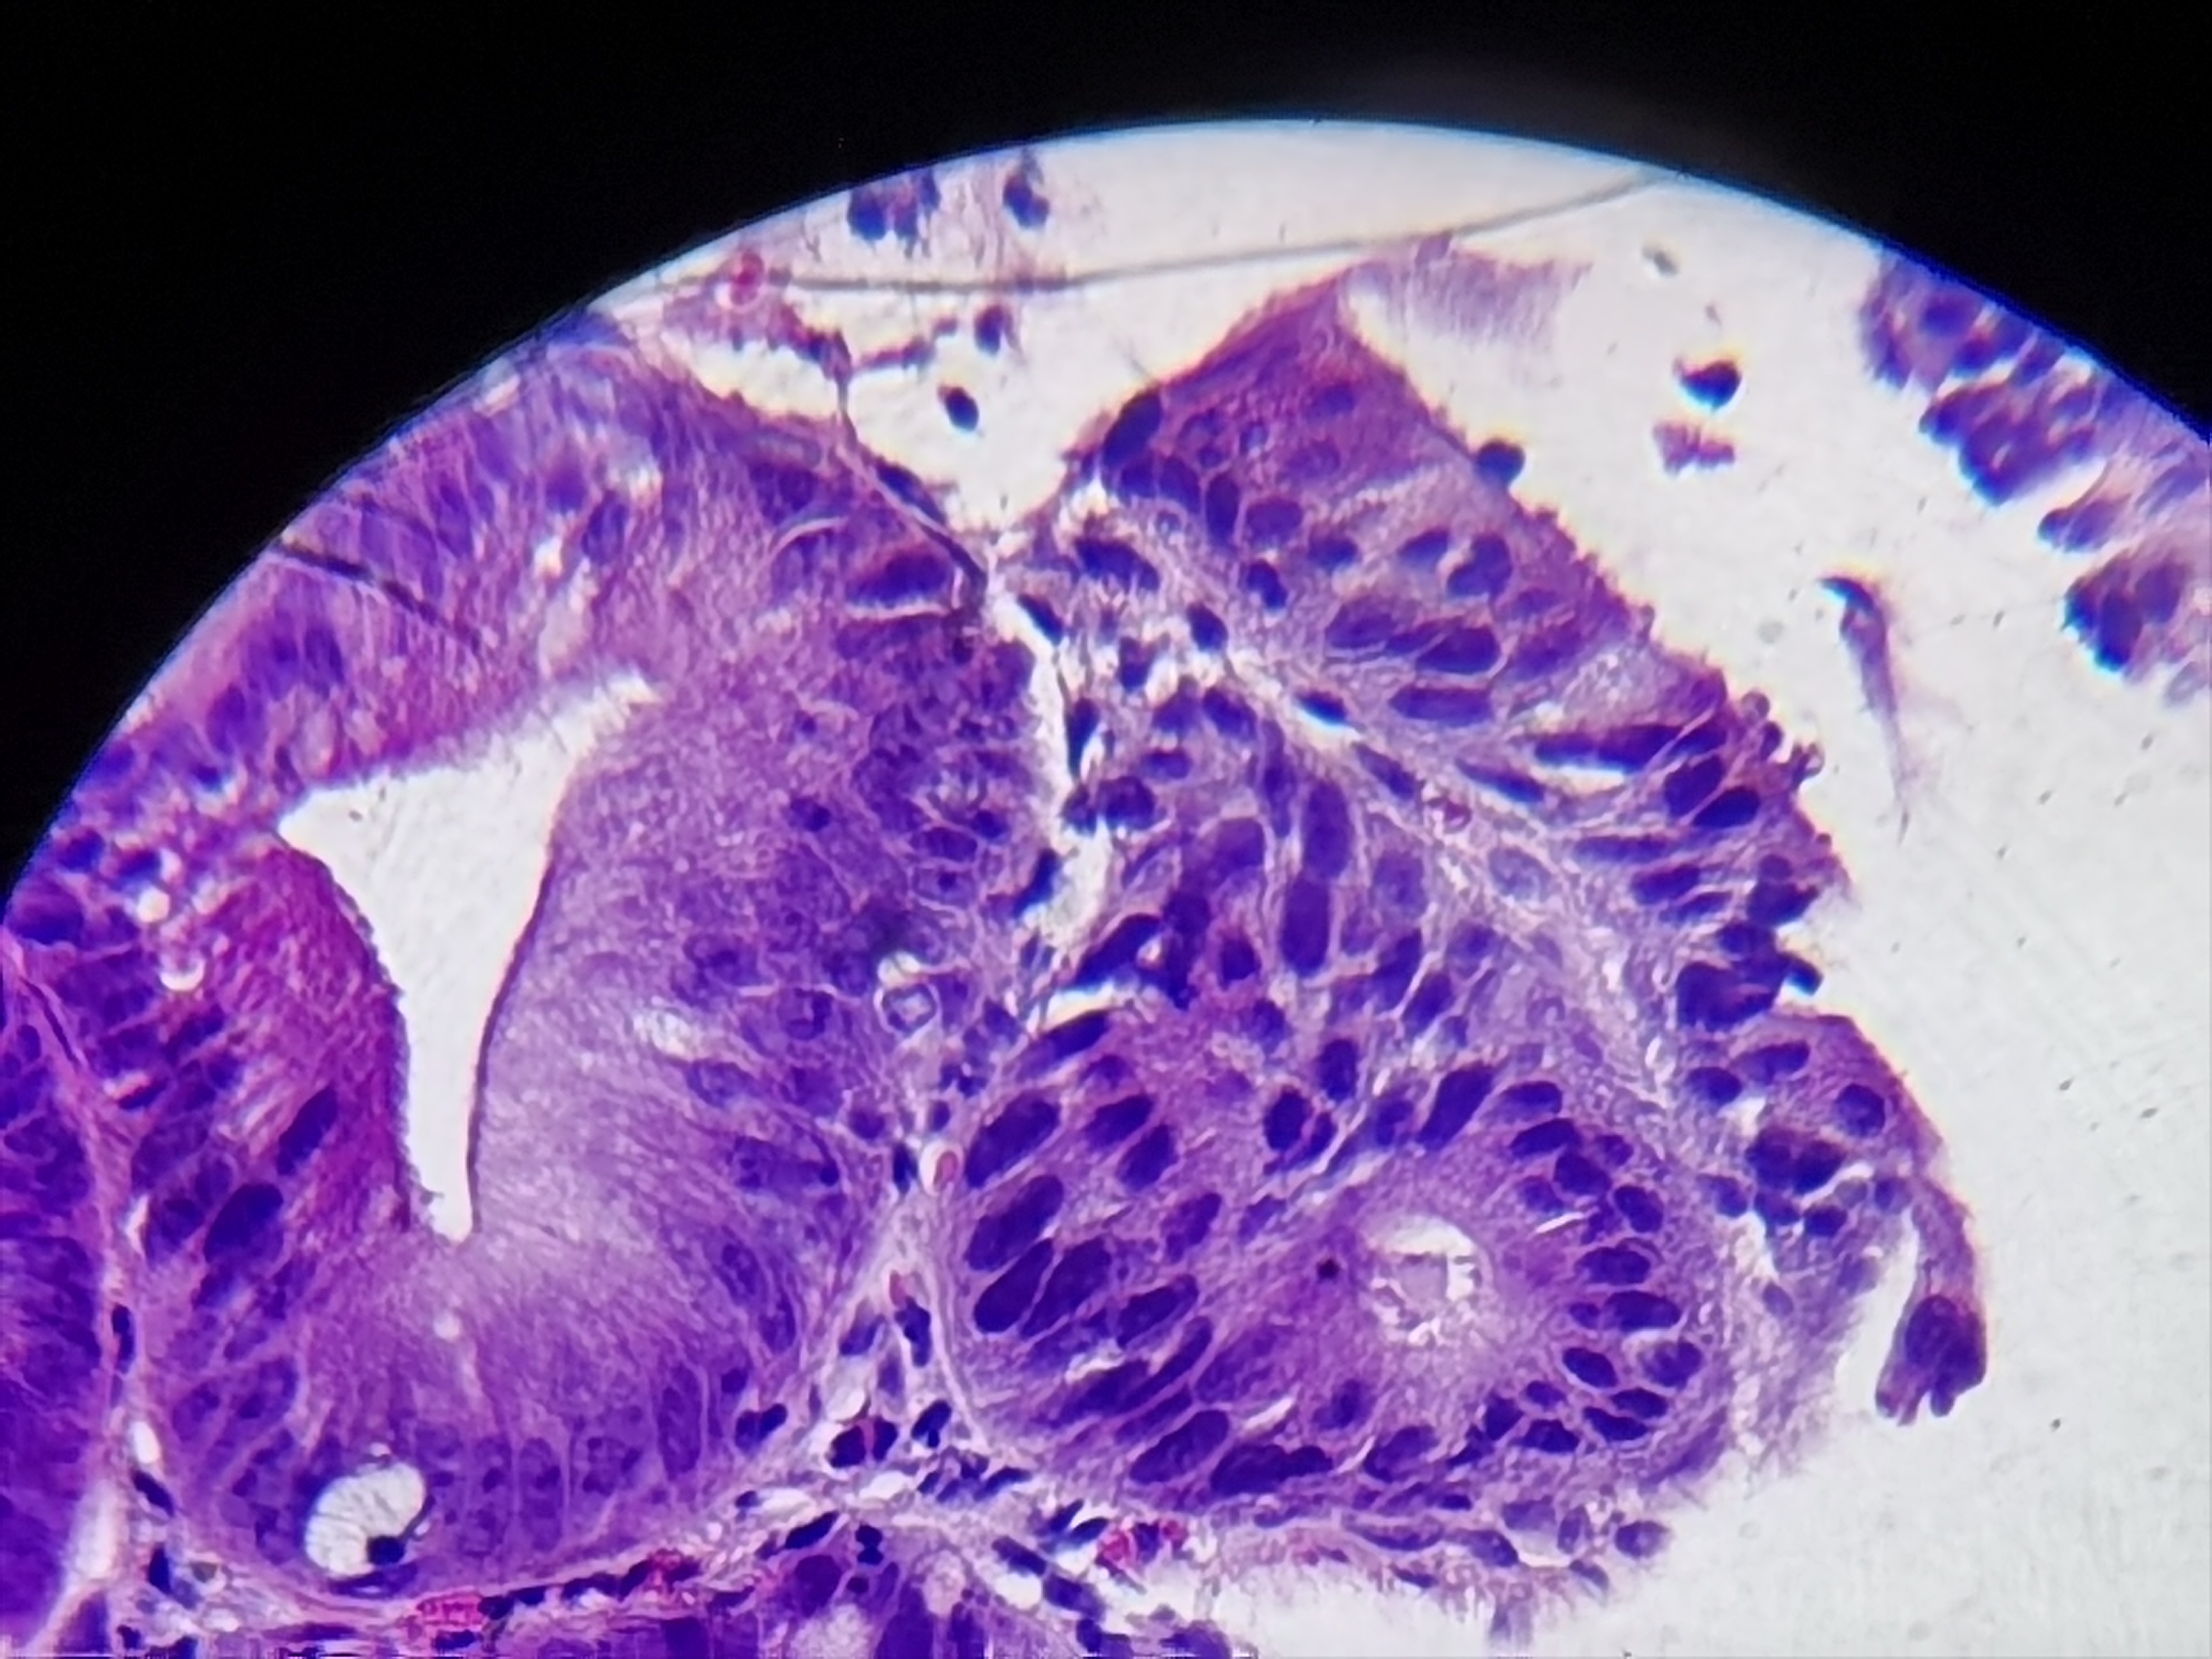

胃角活检

胃角可见粘膜粗糙

胃角粘膜活检

灰白色组织1块

低级别?

图1

低级别

萎缩+肠化+修复